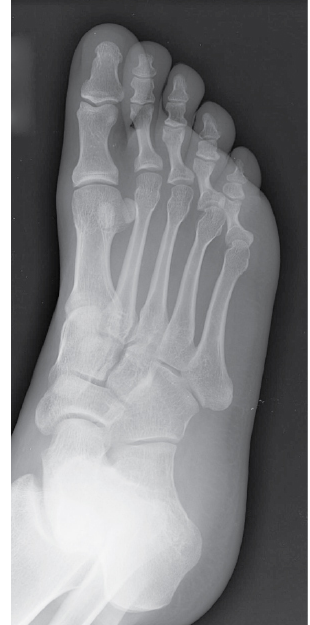

What bone is 3? A - talus B - cuboid C - navicular D - lateral cuneiform

B - cuboid The bones of the foot include the 7 tarsal bones, 5 metatarsal bones, and 14 phalanges. The calcaneus (os calcis), or heel bone, is the largest tarsal (numbers 6 and 7). It serves as attachment for the Achilles tendon posteriorly, articulates anteriorly with the cuboid bone (number 3), presents three articular surfaces superiorly for its articulation with the talus (number 1), and has a prominent shelf on its anteromedial edge called the sustentaculum tali. The inferior surface of the talus (astragalus) articulates with the superior calcaneus to form the three-f